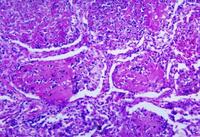

Histopathological changes associated with histoplasmosis of the lung

Dr Martin Hicklin, Public Health Image Library, US Centers for Disease Control and Prevention